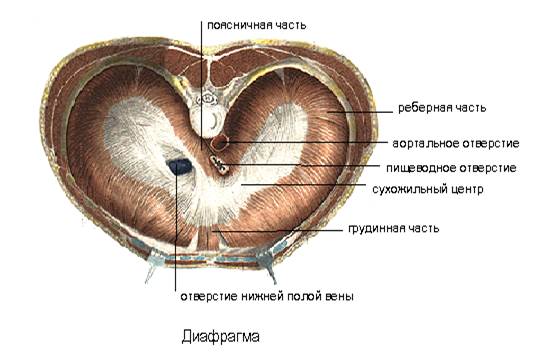

Анатомия диафрагмы и треугольника Бохдалека

Раздел: Визуальный дайджест